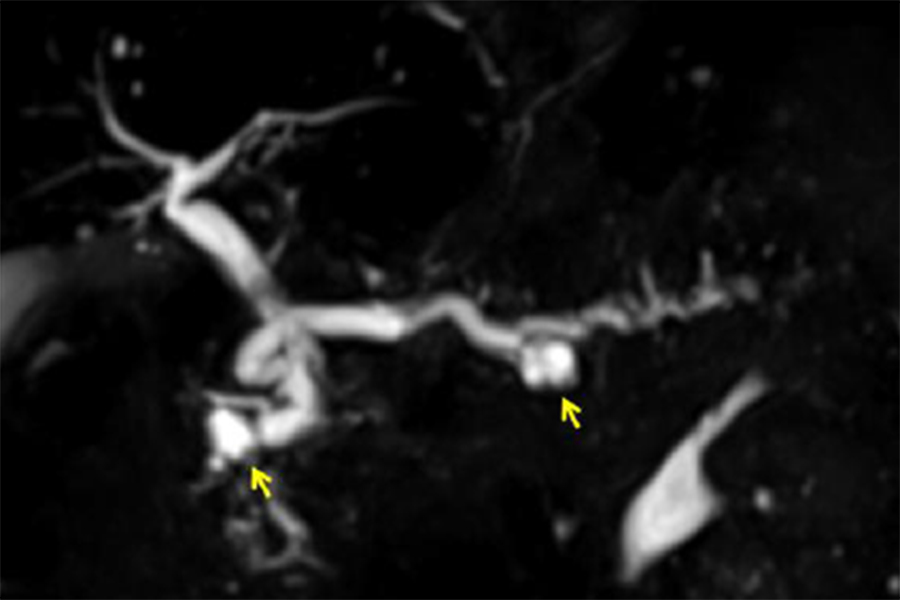

EUS で腫瘤として描出されなくても、膵癌が疑われる所見(主膵管狭窄や限局的な膵実質萎縮など)がある場合は、非常に小さな膵癌の可能性がありますので、ERP(内視鏡を用いた膵管造影検査)を行って膵管内の膵液を採取し、細胞診を行います。最近では、ERPに引き続いて膵管内に細いチューブを 1 日ほど留置し、チューブを介して経鼻的に体外に排出される膵液を繰り返し採取して細胞診に提出する“連続膵液吸引細胞診(SPACE)”という方法を積極的に行っており、早期診断を目指した取り組みを行っています。

写真は、限局性の主膵管狭窄(赤矢印)に対してSPACEを行い、上皮内癌(ステージ0)を診断した症例です。